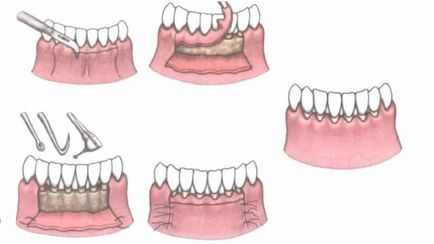

Assigned deschise pungile parodontale chiuretaj pentru eliminarea proceselor inflamatorii, eliminarea depunerilor subgingivali, substituiri tisulară. Această procedură vă permite de asemenea pentru a elimina complet pungile parodontale si ajuta la refacerea țesutului osos naturale, pentru care medicul „implantează„material artificial.

Inainte de operatie, medicul efectuează pregătirea necesară. Purtat de curățare profesională a întregii plăci orale cavitatea, tartru și puroi, dinții splinted (dacă este cazul), i se atribuie un curs de terapie cu antibiotice și agenți antiinflamatori.

La timpul stabilit, pacientul a pus o anestezie regională locală. Operația se realizează pe o anumită zonă, fără a include mai mult de 8 dinți.

Procedura deschisa implica peeling gingie ale mucoasei chirurg periodentist. Pentru a face acest lucru, medicul efectuează o mică incizie în zona de gât dentare. Plasturii obținute se extrage din os, expunând zona rădăcinii dintelui și distrugerea osoasă. În această etapă, medicul vede tot placa complet subgingival și a tartrului și țesut de granulație. Se elimină formarea anormală (inclusiv buzunare) folosind Chiurete chirurgicale. Spitalul moderne permit răzuire tesatura de înlocuire și pietre chiuretă cu ultrasunet. În același mod se pot elimina pungile parodontale (imaginea de mai jos).

Apoi, medicul poartă zona de tratament antiseptic. După purificare prin țesut de granulație rămâne cavitatea goală în interiorul osului. Dentist oferă un lift în care os sintetic crescut.

Acest material artificial stimuleaza refacerea propriei sale tesatura, ceea ce va reduce considerabil adâncimea cavității.

Ultimul pas este împletit în zona în care papilele interdentare. De asemenea, pe zona atribuit un pansament special care protejeaza rana de la infecție și promovează regenerarea țesutului. Medicul elimină cusături după 10 zile.